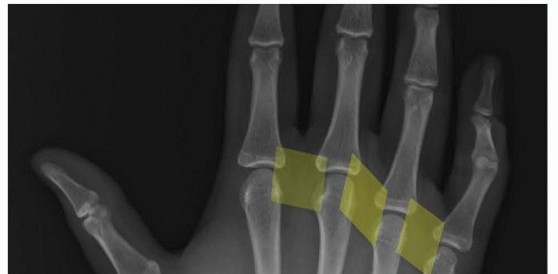

Diagnostic Pitfall: Do not rely solely on contralateral radiographs. To differentiate a fracture from a bipartite sesamoid, evaluate the fragment morphology. Fractured sesamoids typically exhibit roughly equal-sized fragments with irregular, jagged, and uncorticated edges. Conversely, bipartite sesamoids usually present as one large and one small fragment with smooth, rounded, corticated margins.

A comprehensive radiographic series is mandatory:

* Standard AP and Lateral Views: The forefoot should be in slight pronation during the lateral view to properly profile the sesamoids.

* Oblique Views: The medial oblique view isolates the tibial sesamoid, while the lateral oblique view isolates the fibular sesamoid.

* Axial Sesamoid View: Essential for evaluating the articular surface, joint space narrowing, and subchondral sclerosis associated with osteochondritis.

When plain radiographs are equivocal, advanced imaging is warranted. Computed Tomography (CT) provides excellent bony detail for assessing fracture comminution and healing. Radionuclide bone scanning can confirm an active osseous process; however, Chisin et al. caution that 26% to 29% of asymptomatic individuals exhibit increased uptake in the sesamoids. Therefore, bone scan results must be strictly correlated with clinical findings. Magnetic Resonance Imaging (MRI) is increasingly preferred over bone scans due to its superior ability to detect bone marrow edema and evaluate the integrity of the plantar plate and FHB mechanism.